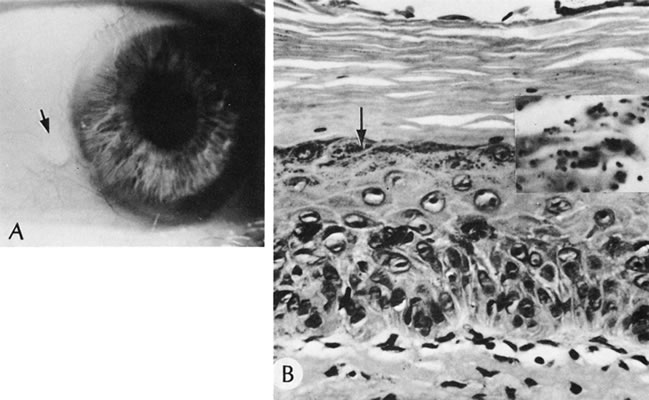

126. Kuwabara T, Ciccarelli E: Meesmann's corneal dystrophy. A pathological

study. Arch Ophthalmol 71:676, 1964.

127. Nakanishi I, Brown SI: Ultrastructure of the epithelial dystrophy

of Meesmann. Arch Ophthalmol 93:259, 1975

128. Irvine AD, Corden LD, Swensson O et al: Mutations in cornea-specific

keratin K3 or K12 genes cause Meesmann's corneal dystrophy. Nat Genet

16:184, 1997.